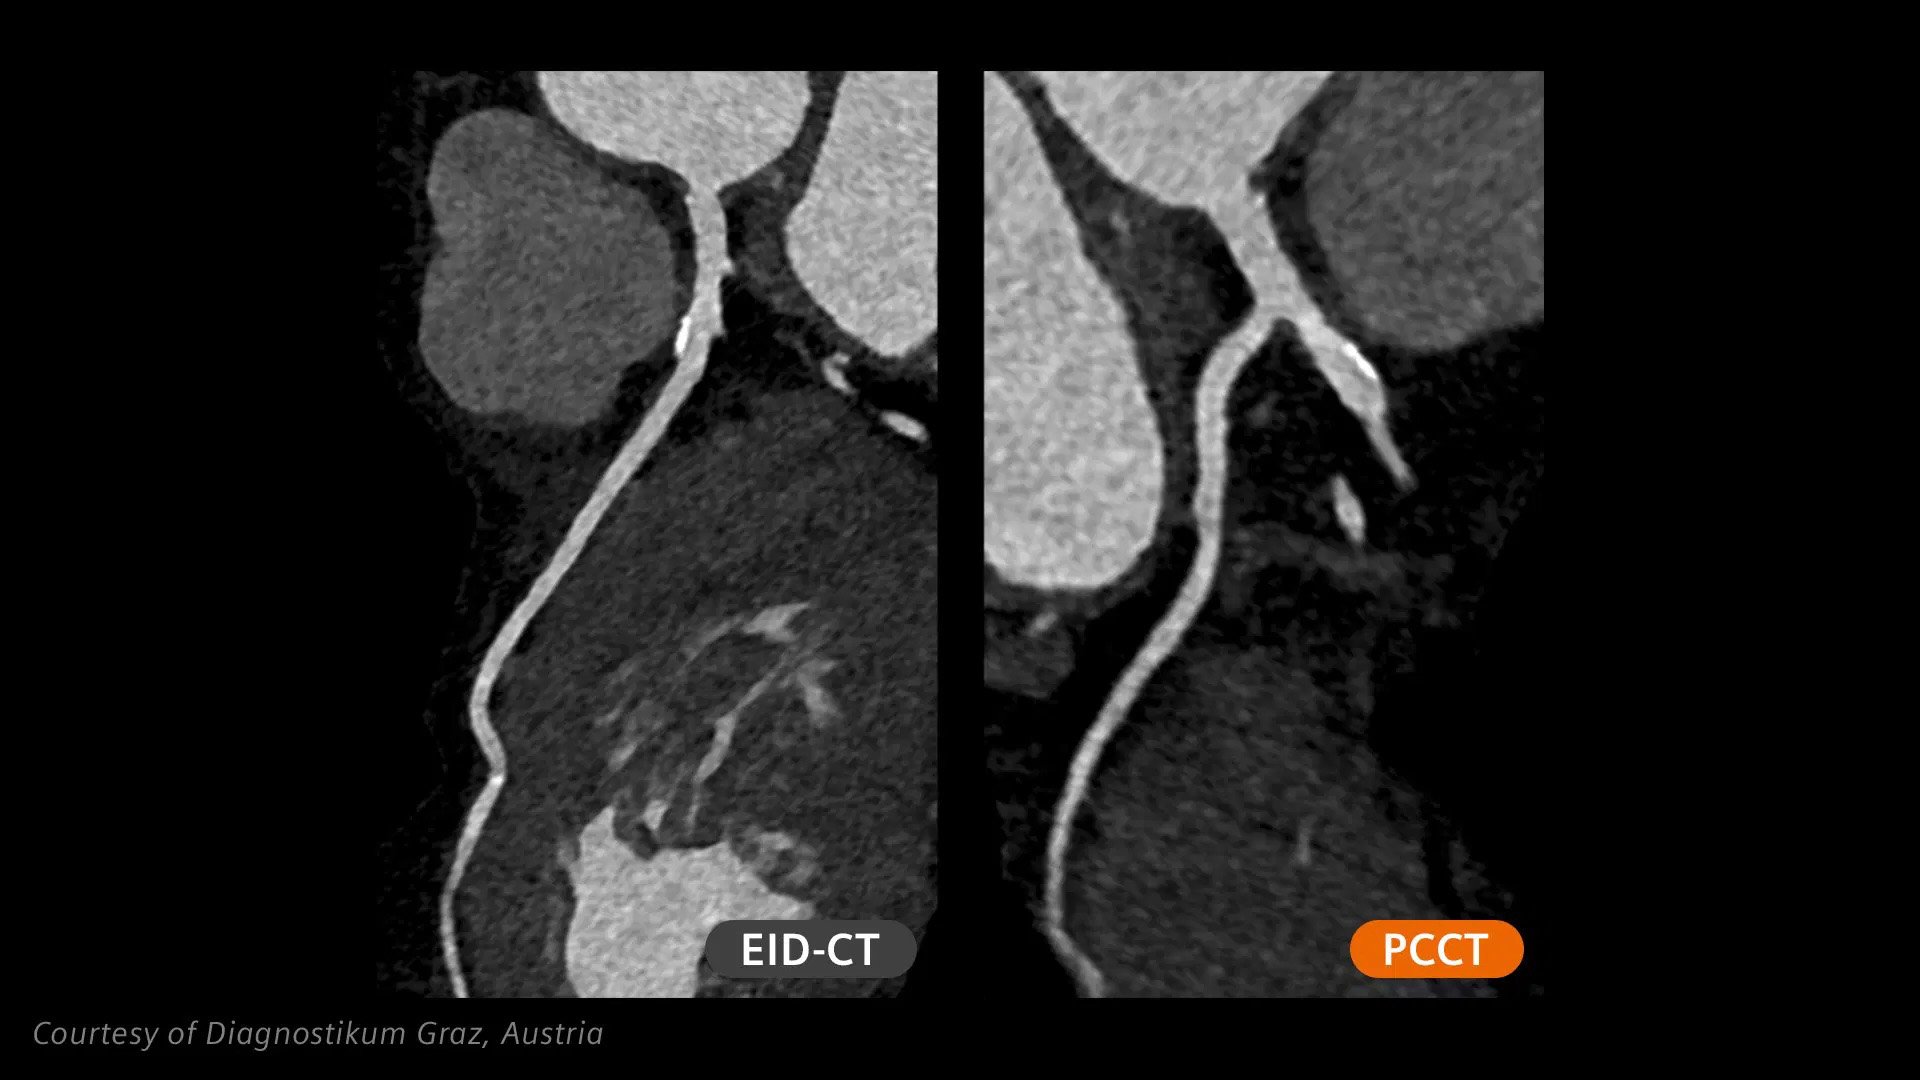

Patients with high calcium scores can now be scanned with photon-counting CT and benefit from Quantum Technology cardiac imaging with reduced stack artifacts enabled by ZeeFree.